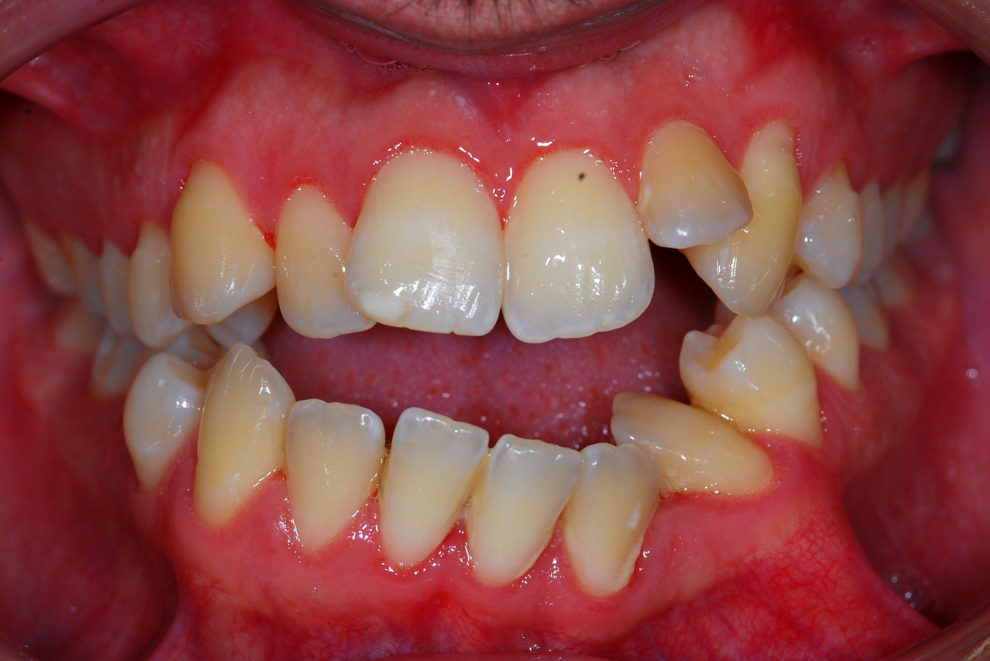

Ortodoncia + Mordida abierta

Nuestro paciente Manuel Vergara Gil acudió a nuestra clínica, y se le hizo una Ortodoncia.